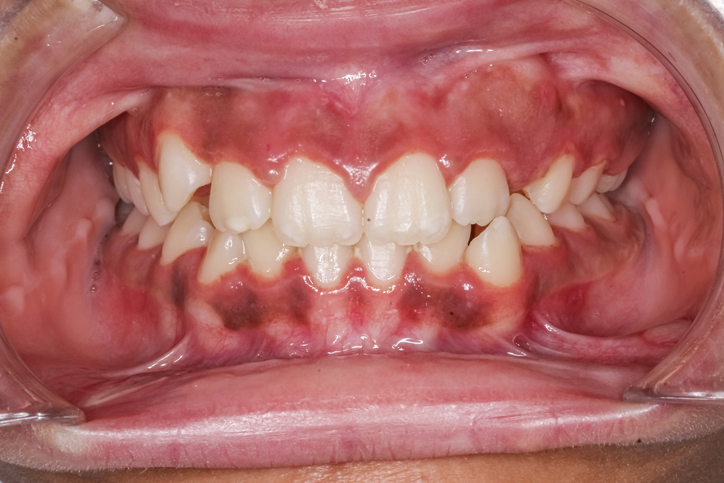

★잇몸 미백은 어두운 색(갈색 또는 검은색)으로 착색된 잇몸을 보다 밝고 건강한 분홍빛으로 되돌리는 치과 시술입니다. 이는 주로 심미적인 이유로 시행되며, 미소를 더욱 깨끗하고 건강하게 보이도록 도와줍니다.

●피부에 멜라닌이 많듯이, 잇몸에도 멜라닌이 많이 분포하면 어두운 색으로 보일 수 있습니다.

●유전적 요인이 큼니다. (특히 동양인, 흑인 등)